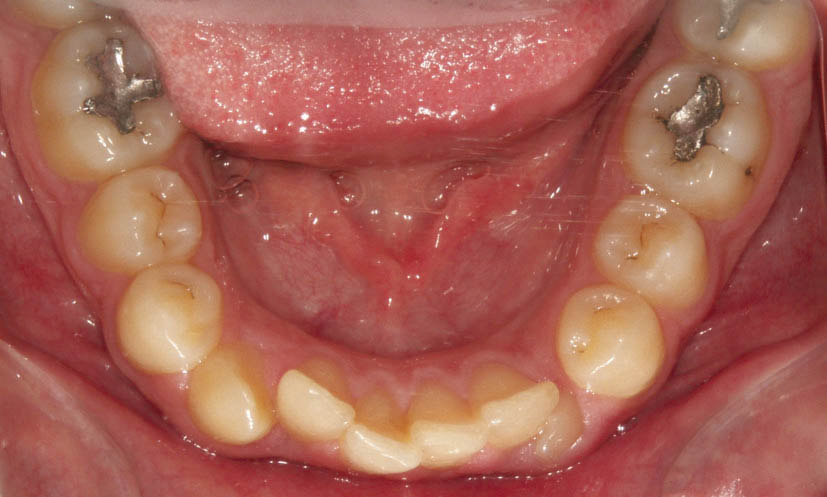

شکل 102-2: نمای اکلوزال پایین